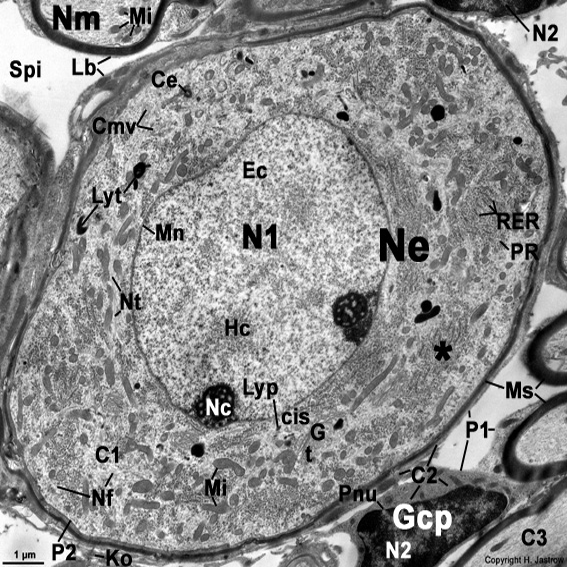

Corpo cellulare di un neurone osservato al TEM

Cmv = corpi multivescicolari; Ec = eucromatina; G = apparato di Golgi; Gcp = cellula gliale del sistema nervoso periferico (cellula di Schwann); Hc = eterocromatina; Ko = fibre collagene; Lb = lamine basali delle cellule gliali; Lyp = lisosoma; Lyt = telolisosomi (granuli di lipofuscina); Mi = mitocondri ; Mn = membrana nucleare; Ms = guaina mielinica; N1 = nucleo della cellula gangliare; N2 = nucleo di una cellula gliale; Nc = nucleolo; Ne = neurone (corpo della cellula nervosa; qui una cellula gangliare bipolare del ganglio spirale cocleare dell’orecchio interno); Nf = neurofilamenti; Nm = processo delle cellule nervose mielinizzate; Nt = Neurotubuli; P1 = Plasmalemma (membrana cellulare) di una cellula gliale; P2 = Plasmalemma (membrana cellulare) della cellula gangliare; Pnu = poro della membrana nucleare; PR = poliribosomi; RER = reticolo endoplasmatico rugoso; Spi = spazio intercellulare); t = parte trans di un apparato del Golgi); * = Corpo di Nissl (ergastoplasma; costituito da RER e PR strettamente aggregati).